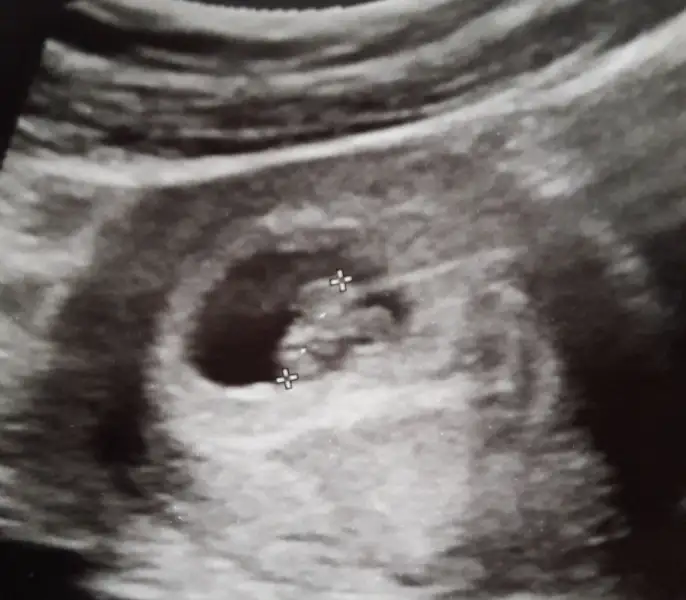

Herkes bebeğinin ultrasonunu atmışş. Bende atayım bari dün kalp atışını ilk defa duyduktan sonra aldım bunu.

Allah sağlıkla kucaklarımıza almamızı nasip etsin. Sağlıklı, hayırlı, mutlu evlatlar olsunlar inşallah :)